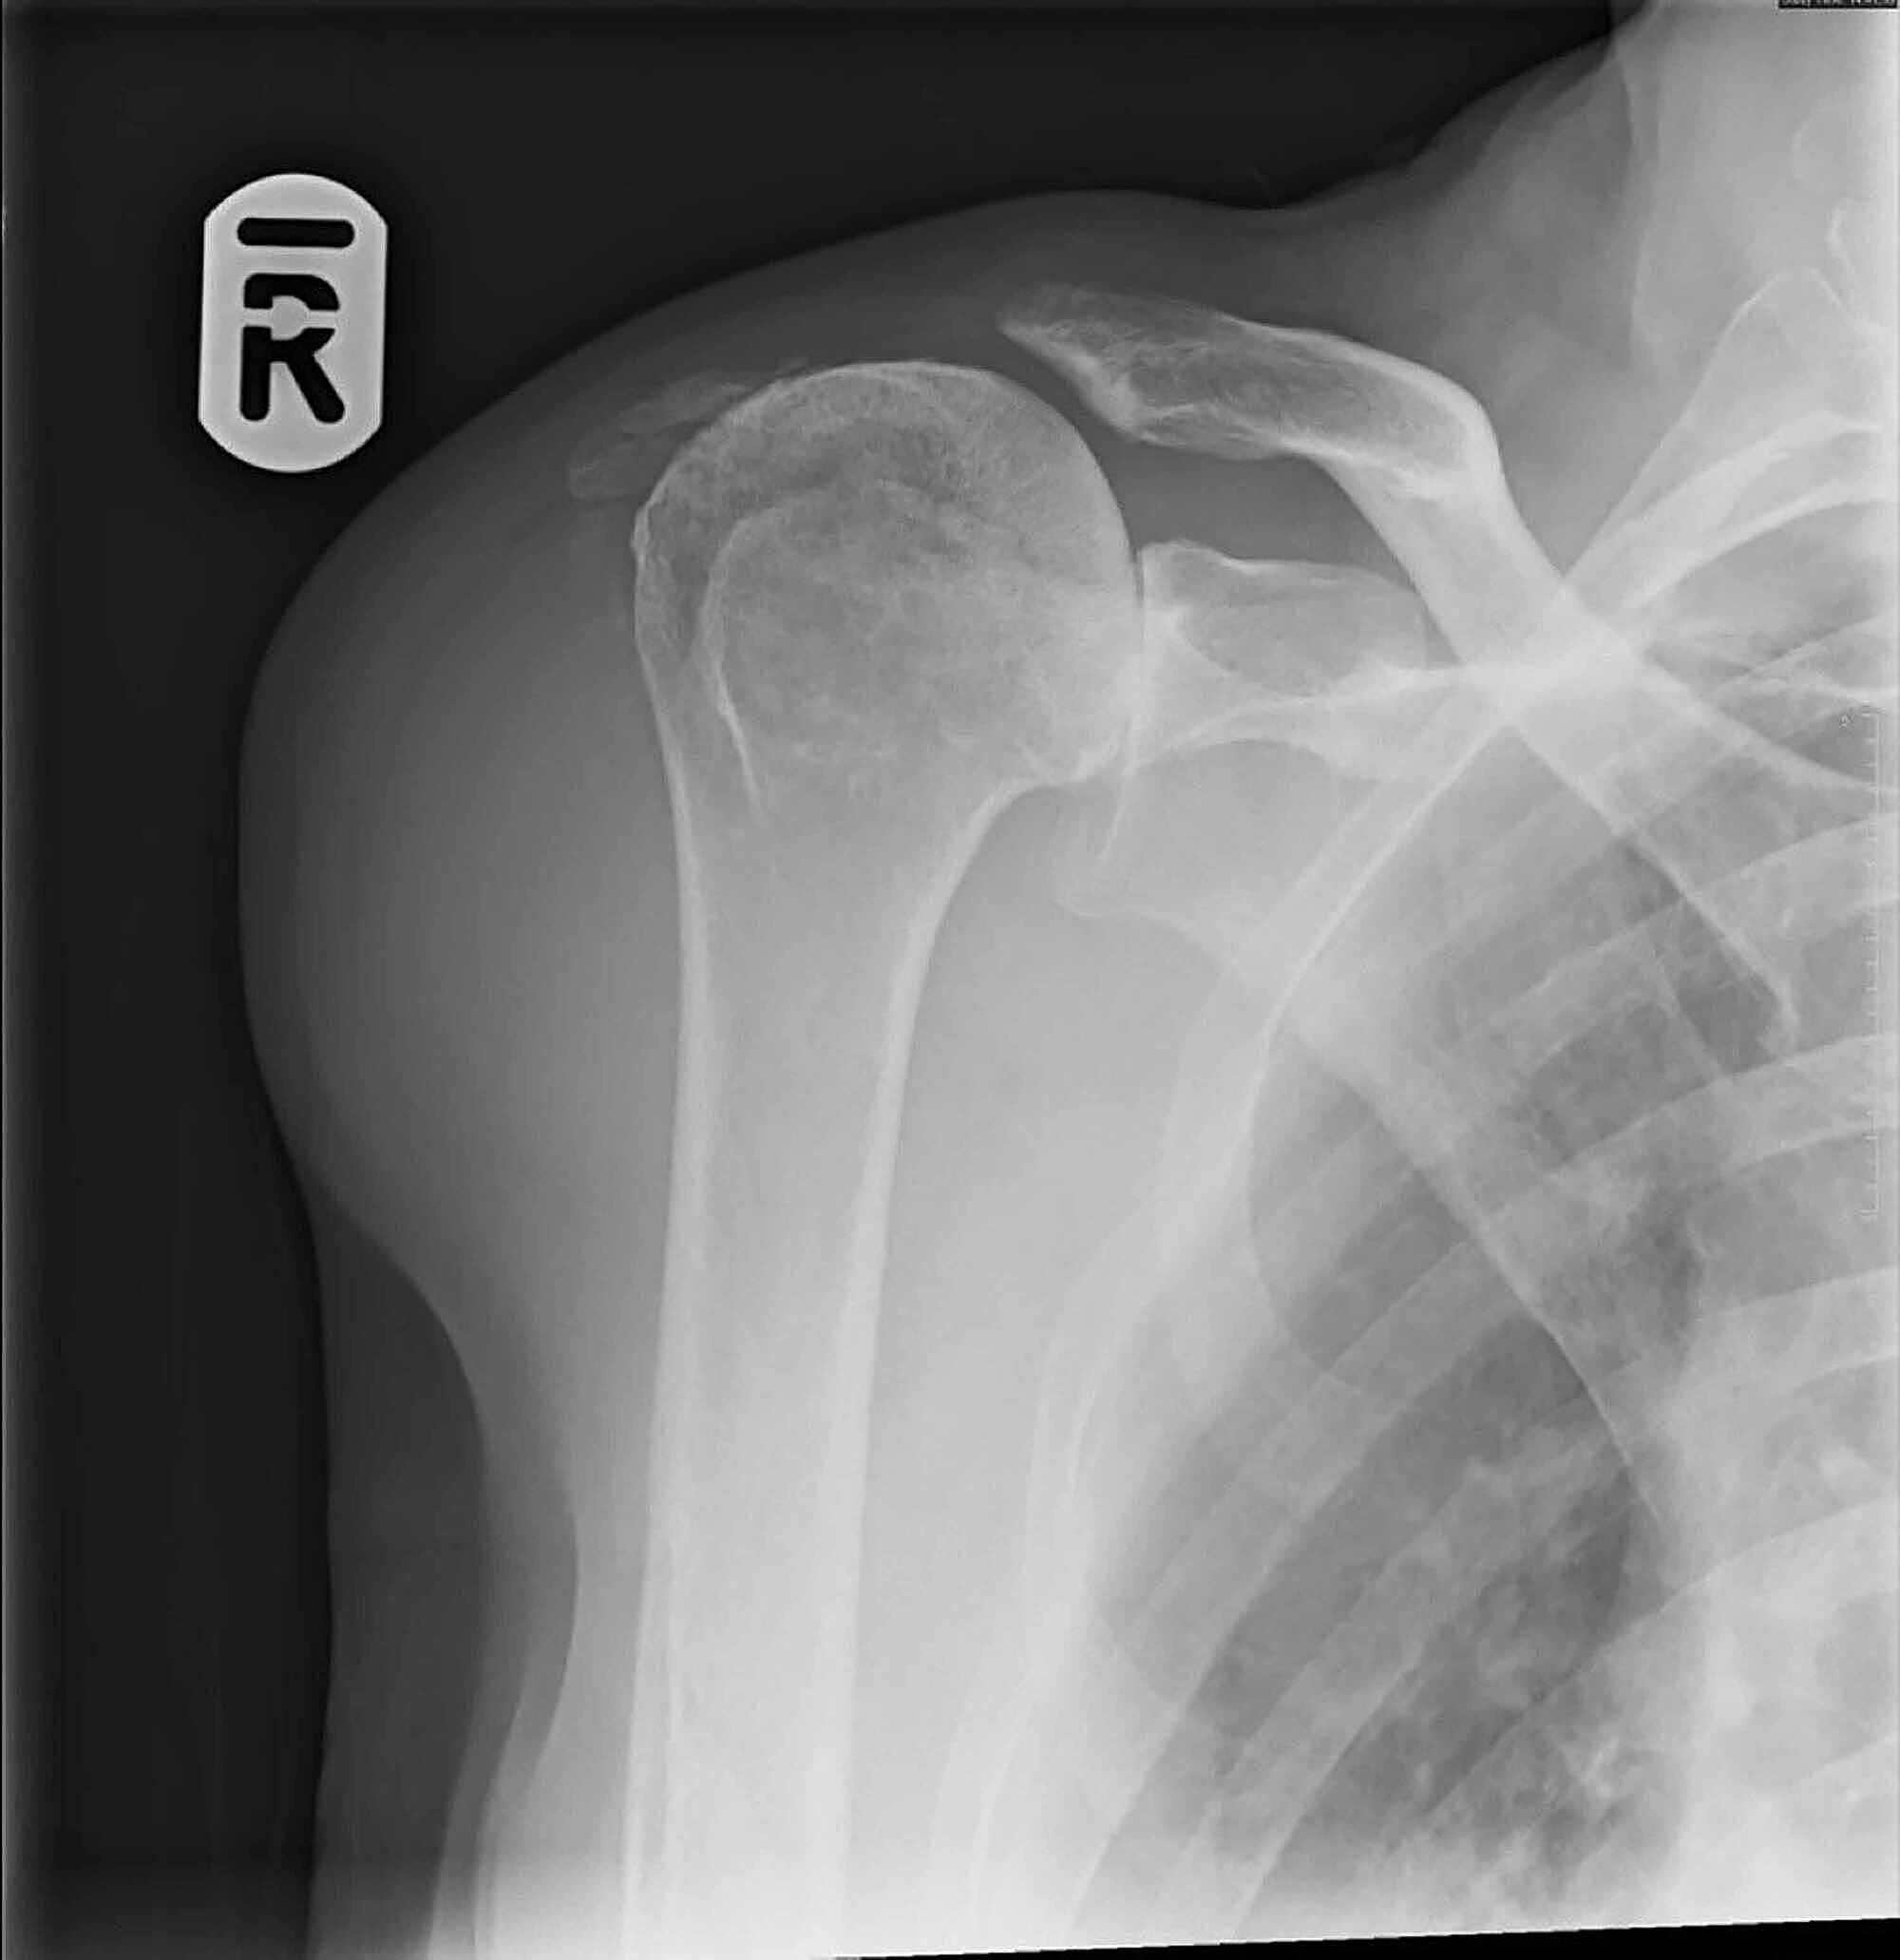

From www.alamy.com

Shoulder xray showing fractured scapula Stock Photo Alamy What Is A Broken Scapula This type of shoulder fracture is. the most common way healthcare providers classify shoulder fractures is by which bone is broken. — the shoulder blade (scapula) is rarely broken (broken bones are also called fractures). The scapula, or shoulder blade, is the triangular bone in the shoulder. The scapula is strong and. the shoulder blade (scapula) is. What Is A Broken Scapula.